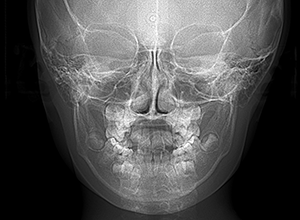

X-Ray

X-Ray所見

セファロ所見 下顎骨体部は大きく下顎枝は前傾しており下顎角は鈍角であった。上顎骨はやや劣位で奥行きがなく下顔面高は高くなっていた。

家族歴や側貌所見、下顎は大きいもののANBは2°でSellaに対して下顎頭は後方に位置していることなどから将来的に重度な下顎前突へ移行することは少ないと予測できた。

パノラマ所見 上顎アーチレングスディスクレパンシー(-)であるが、その他の異常所見は認められなかった。